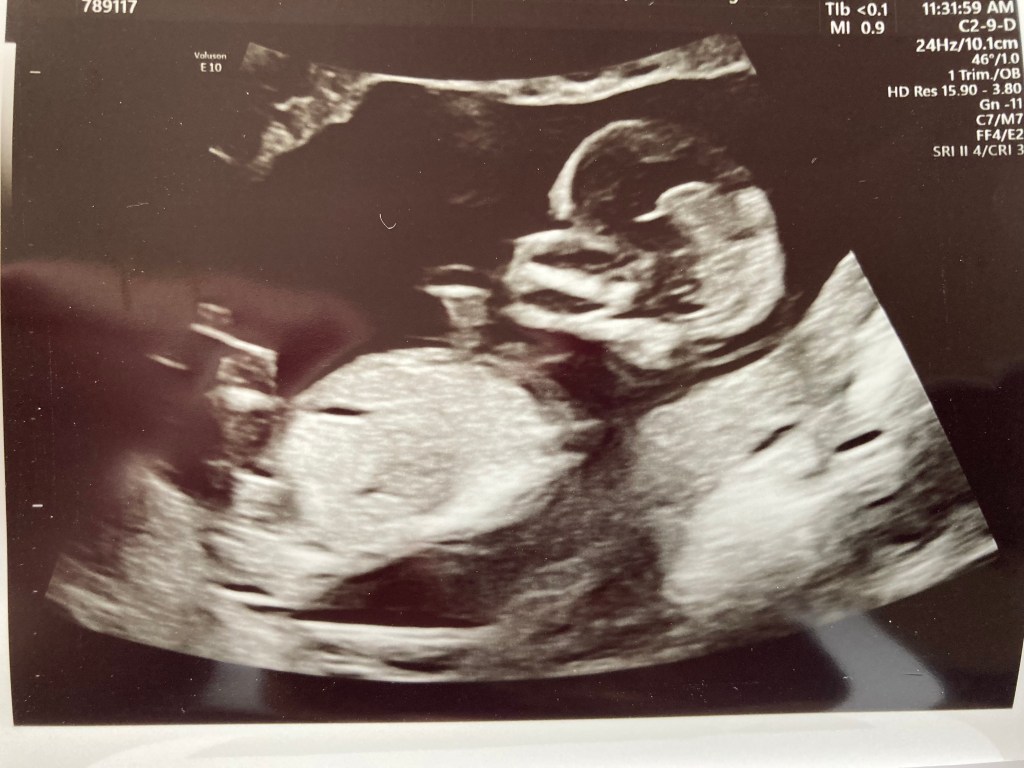

So in my last blog post, I talked briefly about an upcoming project that’s crochet-adjacent, rather than crochet related. I wanted to wait a bit longer to tell you all about it, and you’ll already have seen why in the picture below.

Yep! I’m pregnant!

Thirteen and a half weeks pregnant, to be precise. I wanted to wait until I got through the first trimester to tell you all, and also to wait until I had this scan picture to share 🙂